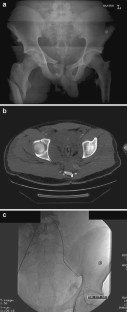

Fig. 2